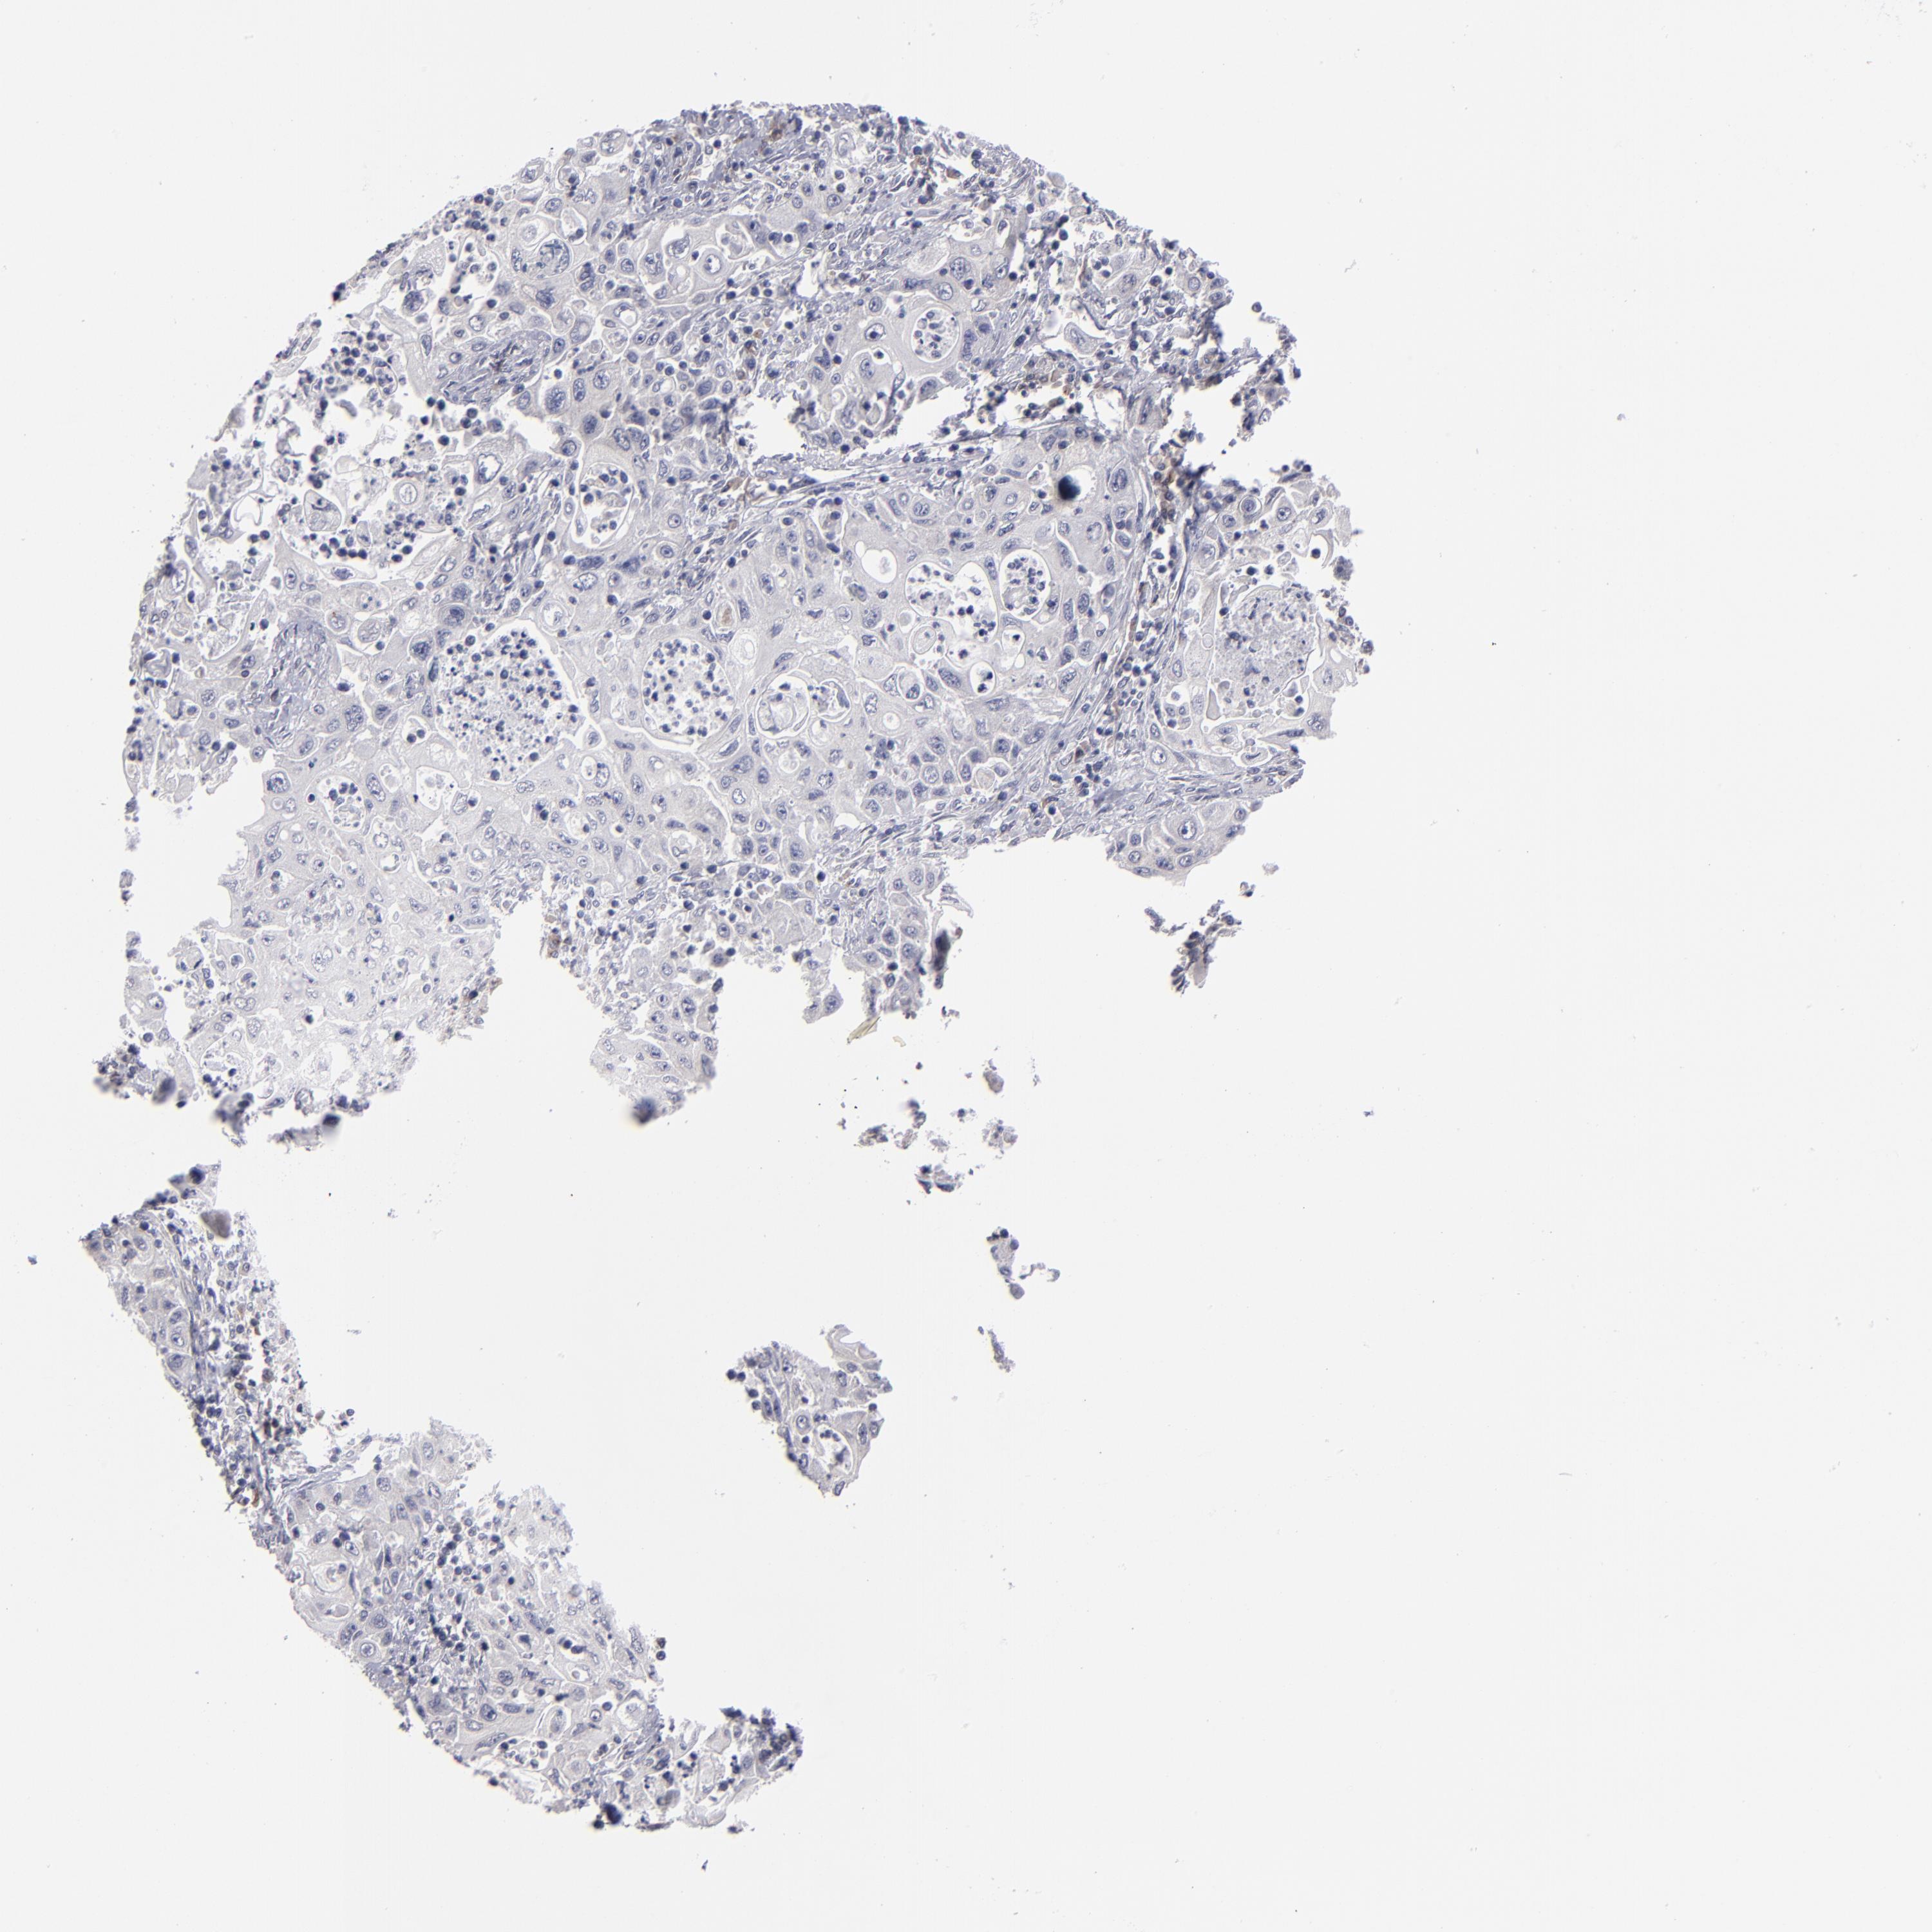

PANCREATIC CANCER - Protein expressioni

A mouse-over function shows sample information and annotation data. Click on an image to view it in a full screen mode. Samples can be filtered based on level of antibody staining by selecting one or several of the following categories: high, medium, low and not detected. The assay and annotation is described here.

Note that samples used for immunohistochemistry by the Human Protein Atlas do not correspond to samples in the TCGA dataset.

Antibody stainingi

Antibody staining in the annotated cell types in the current human tissue is reported as not detected, low, medium, or high, based on conventional immunohistochemistry profiling in selected tissues. This score is based on the combination of the staining intensity and fraction of stained cells.

Each image is clickable and will lead to virtual microscopy that enables deeper exploration of all samples and also displays staining intensity scores, fraction scores and subcellular localization as well as patient and tissue information for each sample.

Antibody HPA002980

Staining

High

Medium

Low

Not detected

Intensity

Strong

Moderate

Weak

Negative

Quantity

>75%

75%-25%

<25%

None

Location

Nuclear

Cytoplasmic/membranous

Cytoplasmic/membranous,nuclear

Adenocarcinoma, NOS